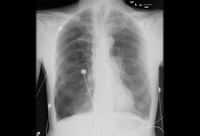

Entrapped lung with pneumothorax ex-vacuo. This patient had a malignant pleural effusion that had developed a thick visceral pleural cortical rind preventing re-expansion. Chest tube was for pleural effusion removal, not evacuation of air.

From the personal collection of Chris Kapp, MD; used with permission